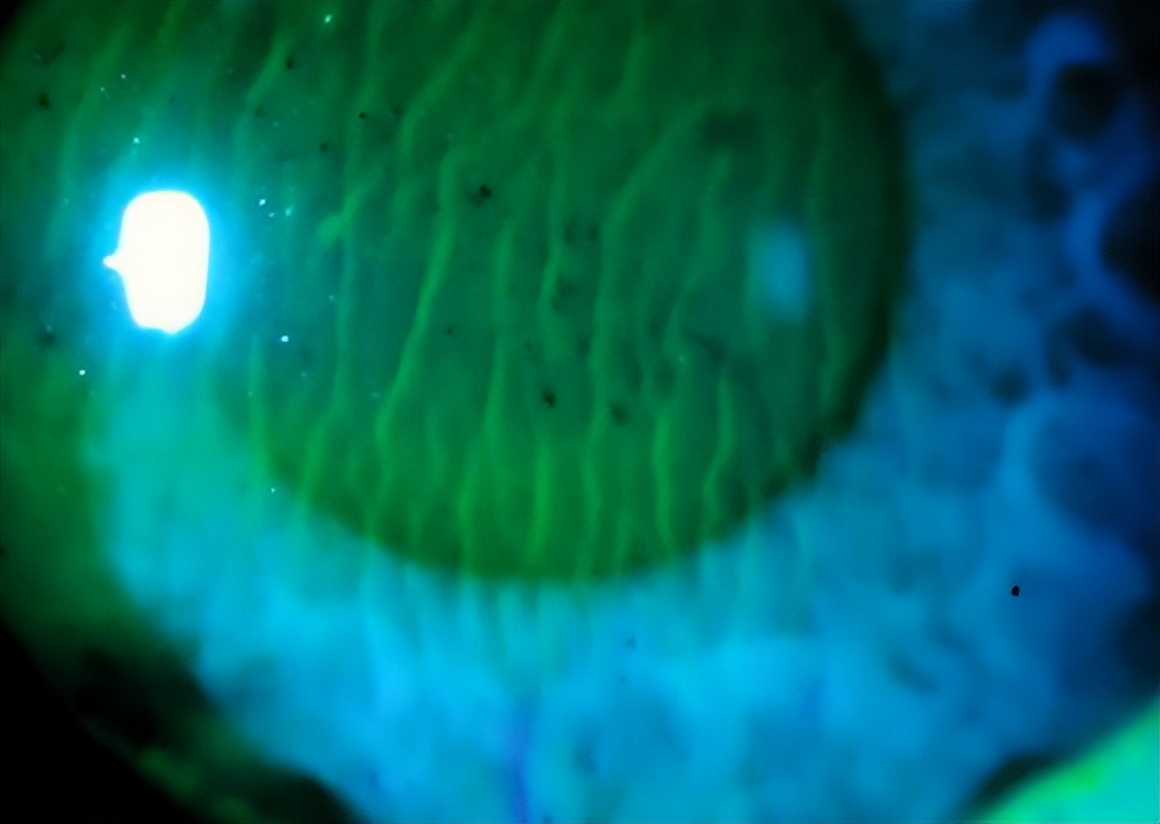

图2. Shah测试发现睫状体离断患者Bowman膜出现明显的皱褶

最后,金教授列举了一个临床病例,展示巩膜层间缝纫机技术的实际应用。患者右眼大范围虹膜根部离断,采用金教授原创的巩膜层间缝纫机技术进行了虹膜修复术,并植入散光矫正型人工晶状体,术后一天患者右眼眼前节正常解剖结构基本恢复,视力显著提高,且未出现低眼压、视网膜脱离等并发症。

图11. 术前患者眼前段照相